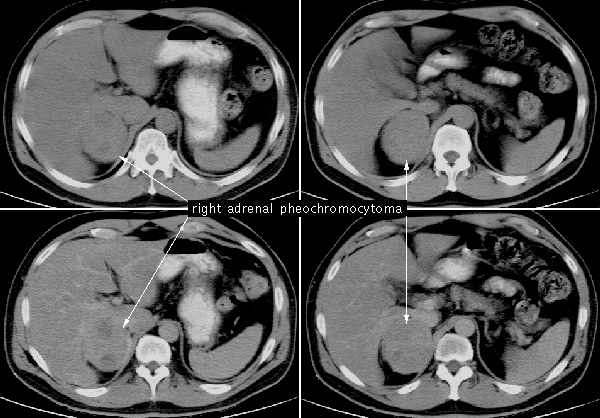

Феохромоцитома

Опухоль затрагивает мозговое вещество НП и производит катехоламины, такие как адреналин и норадреналин. В 90% случаев она является доброкачественной, однако может вызвать серьезные осложнения. Злокачественная форма опухоли опасна своим необычным расположением вне железы. Исследования показывают, что 10% случаев имеют наследственный (семейный) характер. Чаще всего заболевание затрагивает женщин в возрасте от 30 до 50 лет и проявляется через частые изнурительные вегетативные кризы. Болезнь может проявляться в трех формах:

Для подтверждения диагноза эндокринолог может использовать не только традиционные методы диагностики опухолей, такие как УЗИ, КТ с контрастированием и МРТ, но и дополнительные исследования: